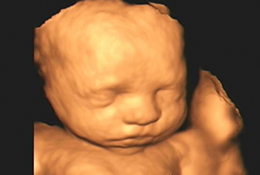

Com alta tecnologia realizamos diversos tipos de ultrassonografias: Obstétrica, Obstétrica com Doppler, Morfológica, 4D, Transvaginal, Transvaginal para pesquisa de Endometriose, Abdominal, Mamas, Tireoide e outros.